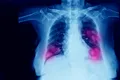

Rezultate „impresionante”: O pastilă reduce riscul de deces în urma cancerului pulmonar